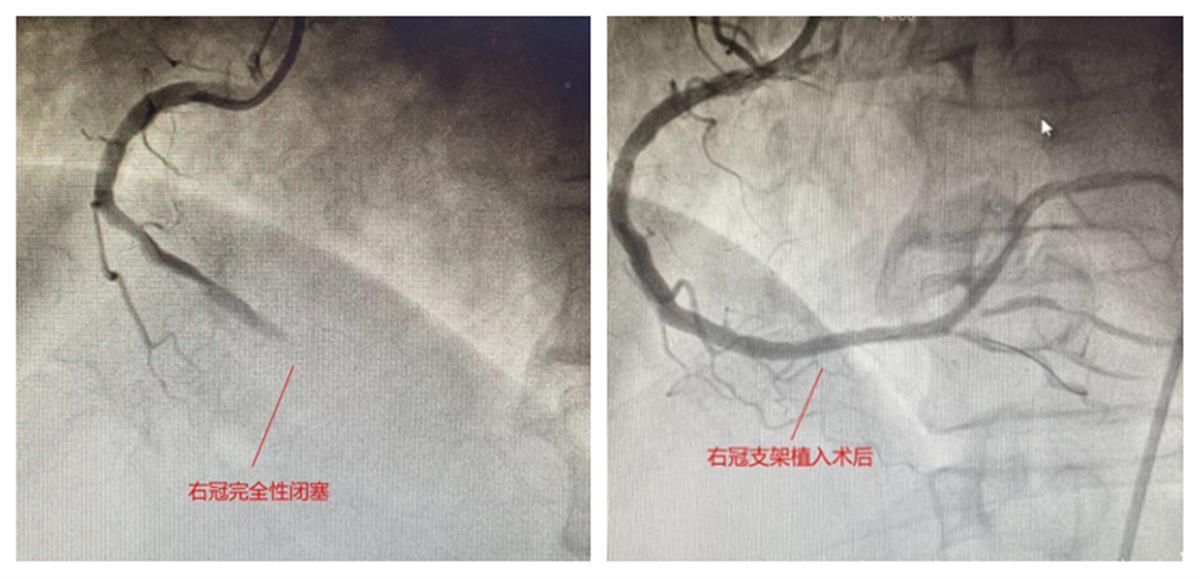

陆先生血管造影图

考虑患者心梗发作与心脏冠脉血管某段(或多段)闭塞引起严重的血流动力学障碍及心室“电风暴”(俗称“电风暴”)有关,“当务之急要尽快锁定并复通血管通路!”为了抓住手术时机,余稳即刻组织医护人员将患者转入心脏介入导管室。心血管介入专家吴兴安、余稳运用穿刺造影以及介入技术,精准锁定并迅速开通了完全闭塞的右冠状动脉远段血管,植入支架。冠脉瞬间恢复血流灌注,“电风暴”得以完全控制。陆先生的各项生命体征逐渐平稳,终得平安。此时,紧张的医护人员才算松了一口气。